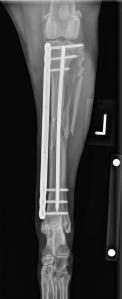

Patient with a Sliding Humeral Osteotomy (SHO).